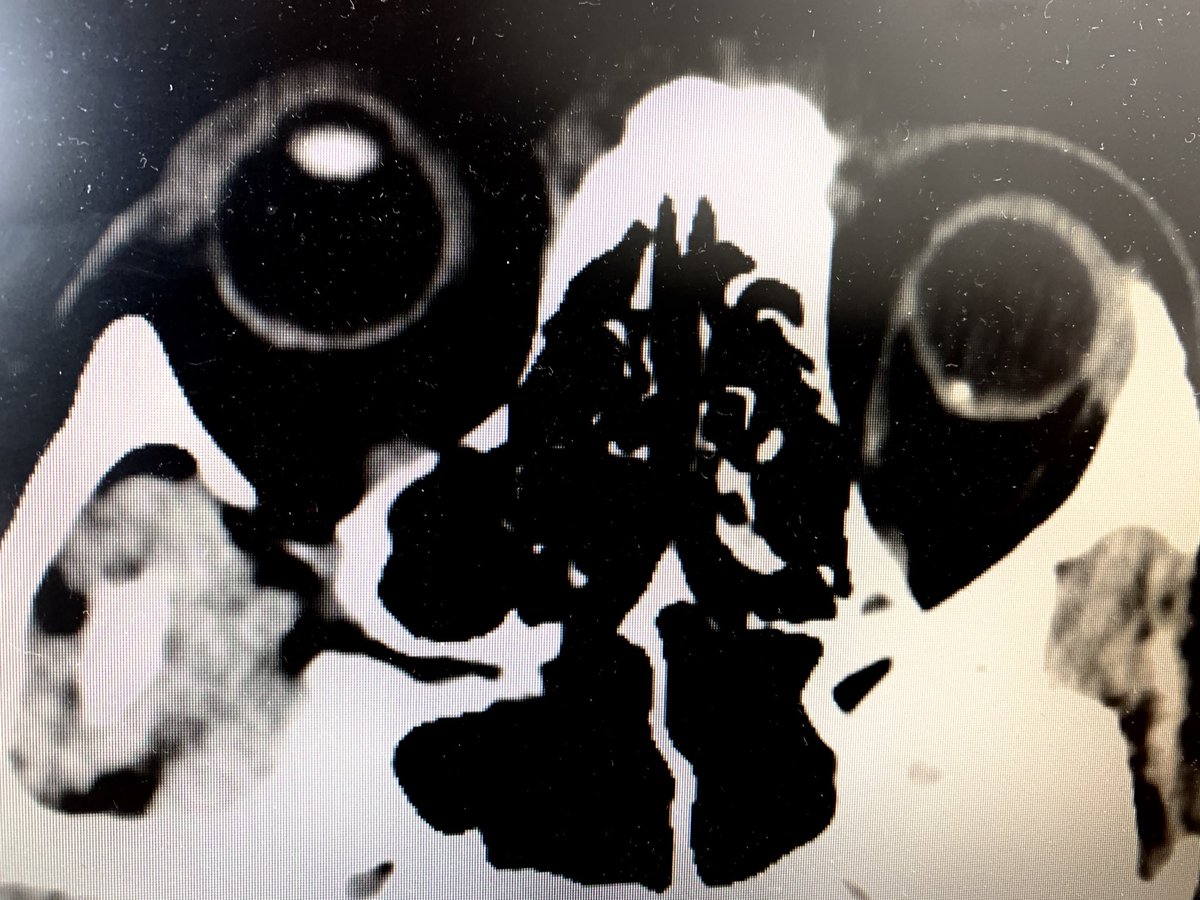

Cool thing of the day: calcified drusen on plain CTpic.twitter.com/nMPb0qlPrv